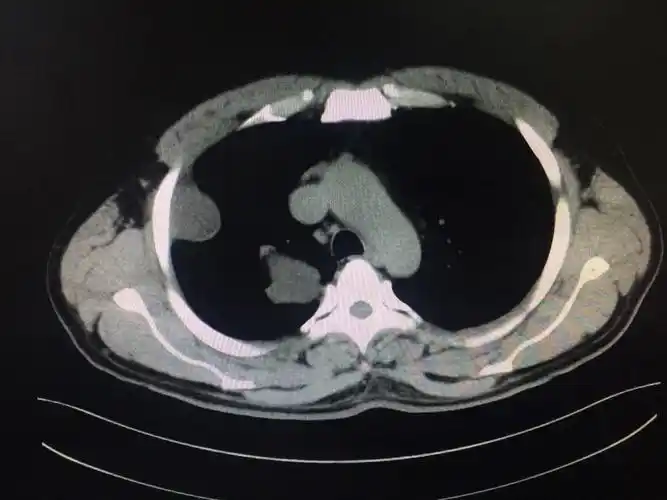

肺包虫囊肿

肺内包虫